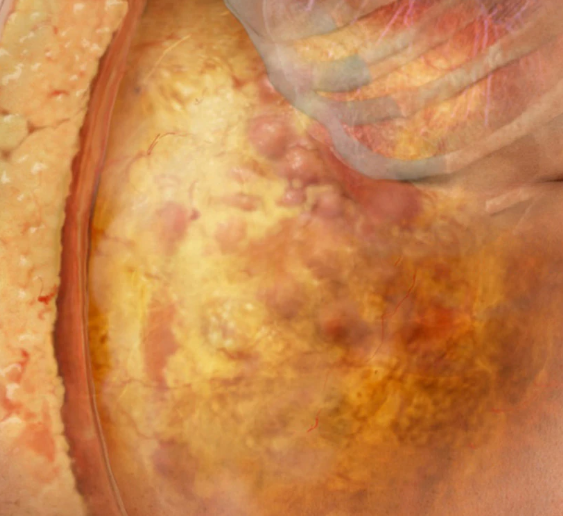

يؤدي تراكم دهون البطن إلى مخاطر صحية كبيرة، مثل أمراض القلب، وقد اكتشف علماء الصحة أن بعض الأطعمة يمكن أن تؤدي إلى انخفاض مستويات هذه الدهون.

واستطاع الباحثون إثبات وجود علاقة بين زيادة الألياف القابلة للذوبان وانخفاض الدهون، قائلين إن لكل 10 غرامات زيادة في الألياف القابلة للذوبان، انخفض معدل تراكم الأنسجة الدهنية بنسبة 3.7%.

دراسة استمرت 5 سنوات

واستندت هذه البيانات إلى دراسة 1114 شخصًا على مدار فترة خمس سنوات حيث تم قياس الدهون للمشاركين بواسطة الأشعة المقطعية، كما طُلب من الأشخاص إكمال استبيانات تستند إلى وجباتهم الغذائية.

الأطعمة الغنية بالألياف القابلة للذوبان

يمكن العثور على الألياف القابلة للذوبان في الشوفان والبازلاء والفول والتفاح والحمضيات والجزر.

ما هي الألياف القابلة للذوبان؟

أوضح مركز Mayo Clinic الأمريكي أن هذا النوع من الألياف يذوب في الماء ليشكل مادة تشبه الهلام، ويمكن للألياف الغذائية أن تقلل من خطر الإصابة بأمراض القلب والأوعية الدموية ومرض السكري النوع 2.

وتحتوي الأطعمة مثل الشوفان والشعير على نوع من الألياف يعرف باسم بيتا غلوكان، والذي قد يساعد في تقليل مستويات الكوليسترول إذا كنت تستهلك 3 غرامات أو أكثر منه يوميًا، كجزء من نظام غذائي صحي.

وتقلل الألياف القابلة للذوبان من خطر الإصابة بأمراض القلب من خلال 4 طرق:

1- منع ارتفاع نسبة السكر في الدم من إتلاف جدران الشرايين.

2- التخلص من الكوليسترول.

3- تقليل مستويات الدهون.

4- المساعدة في منع مقاومة الأنسولين.